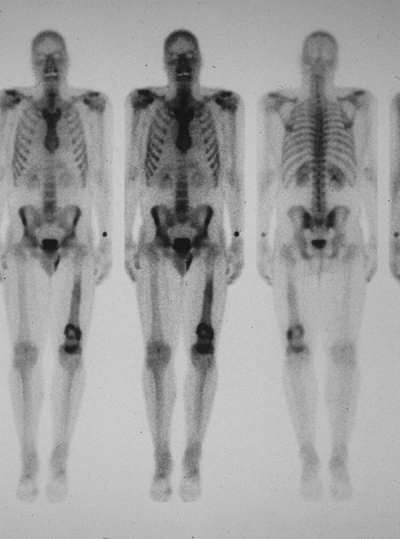

Lesions with radioisotope uptake are more likely to be chondrosarcoma than enchondroma, especially in long bones.

Bone scan may play a role in screening

malignant transformation of enchondroma into chondrosarcoma if serial

examinations are available. -

Some enchondromas can exhibit uptake of radioisotope.

-

May have a role in tumor grading in chondrosarcoma

Figure 6.3-8 Bone scan of patient with left distal femoral chondrosarcoma.